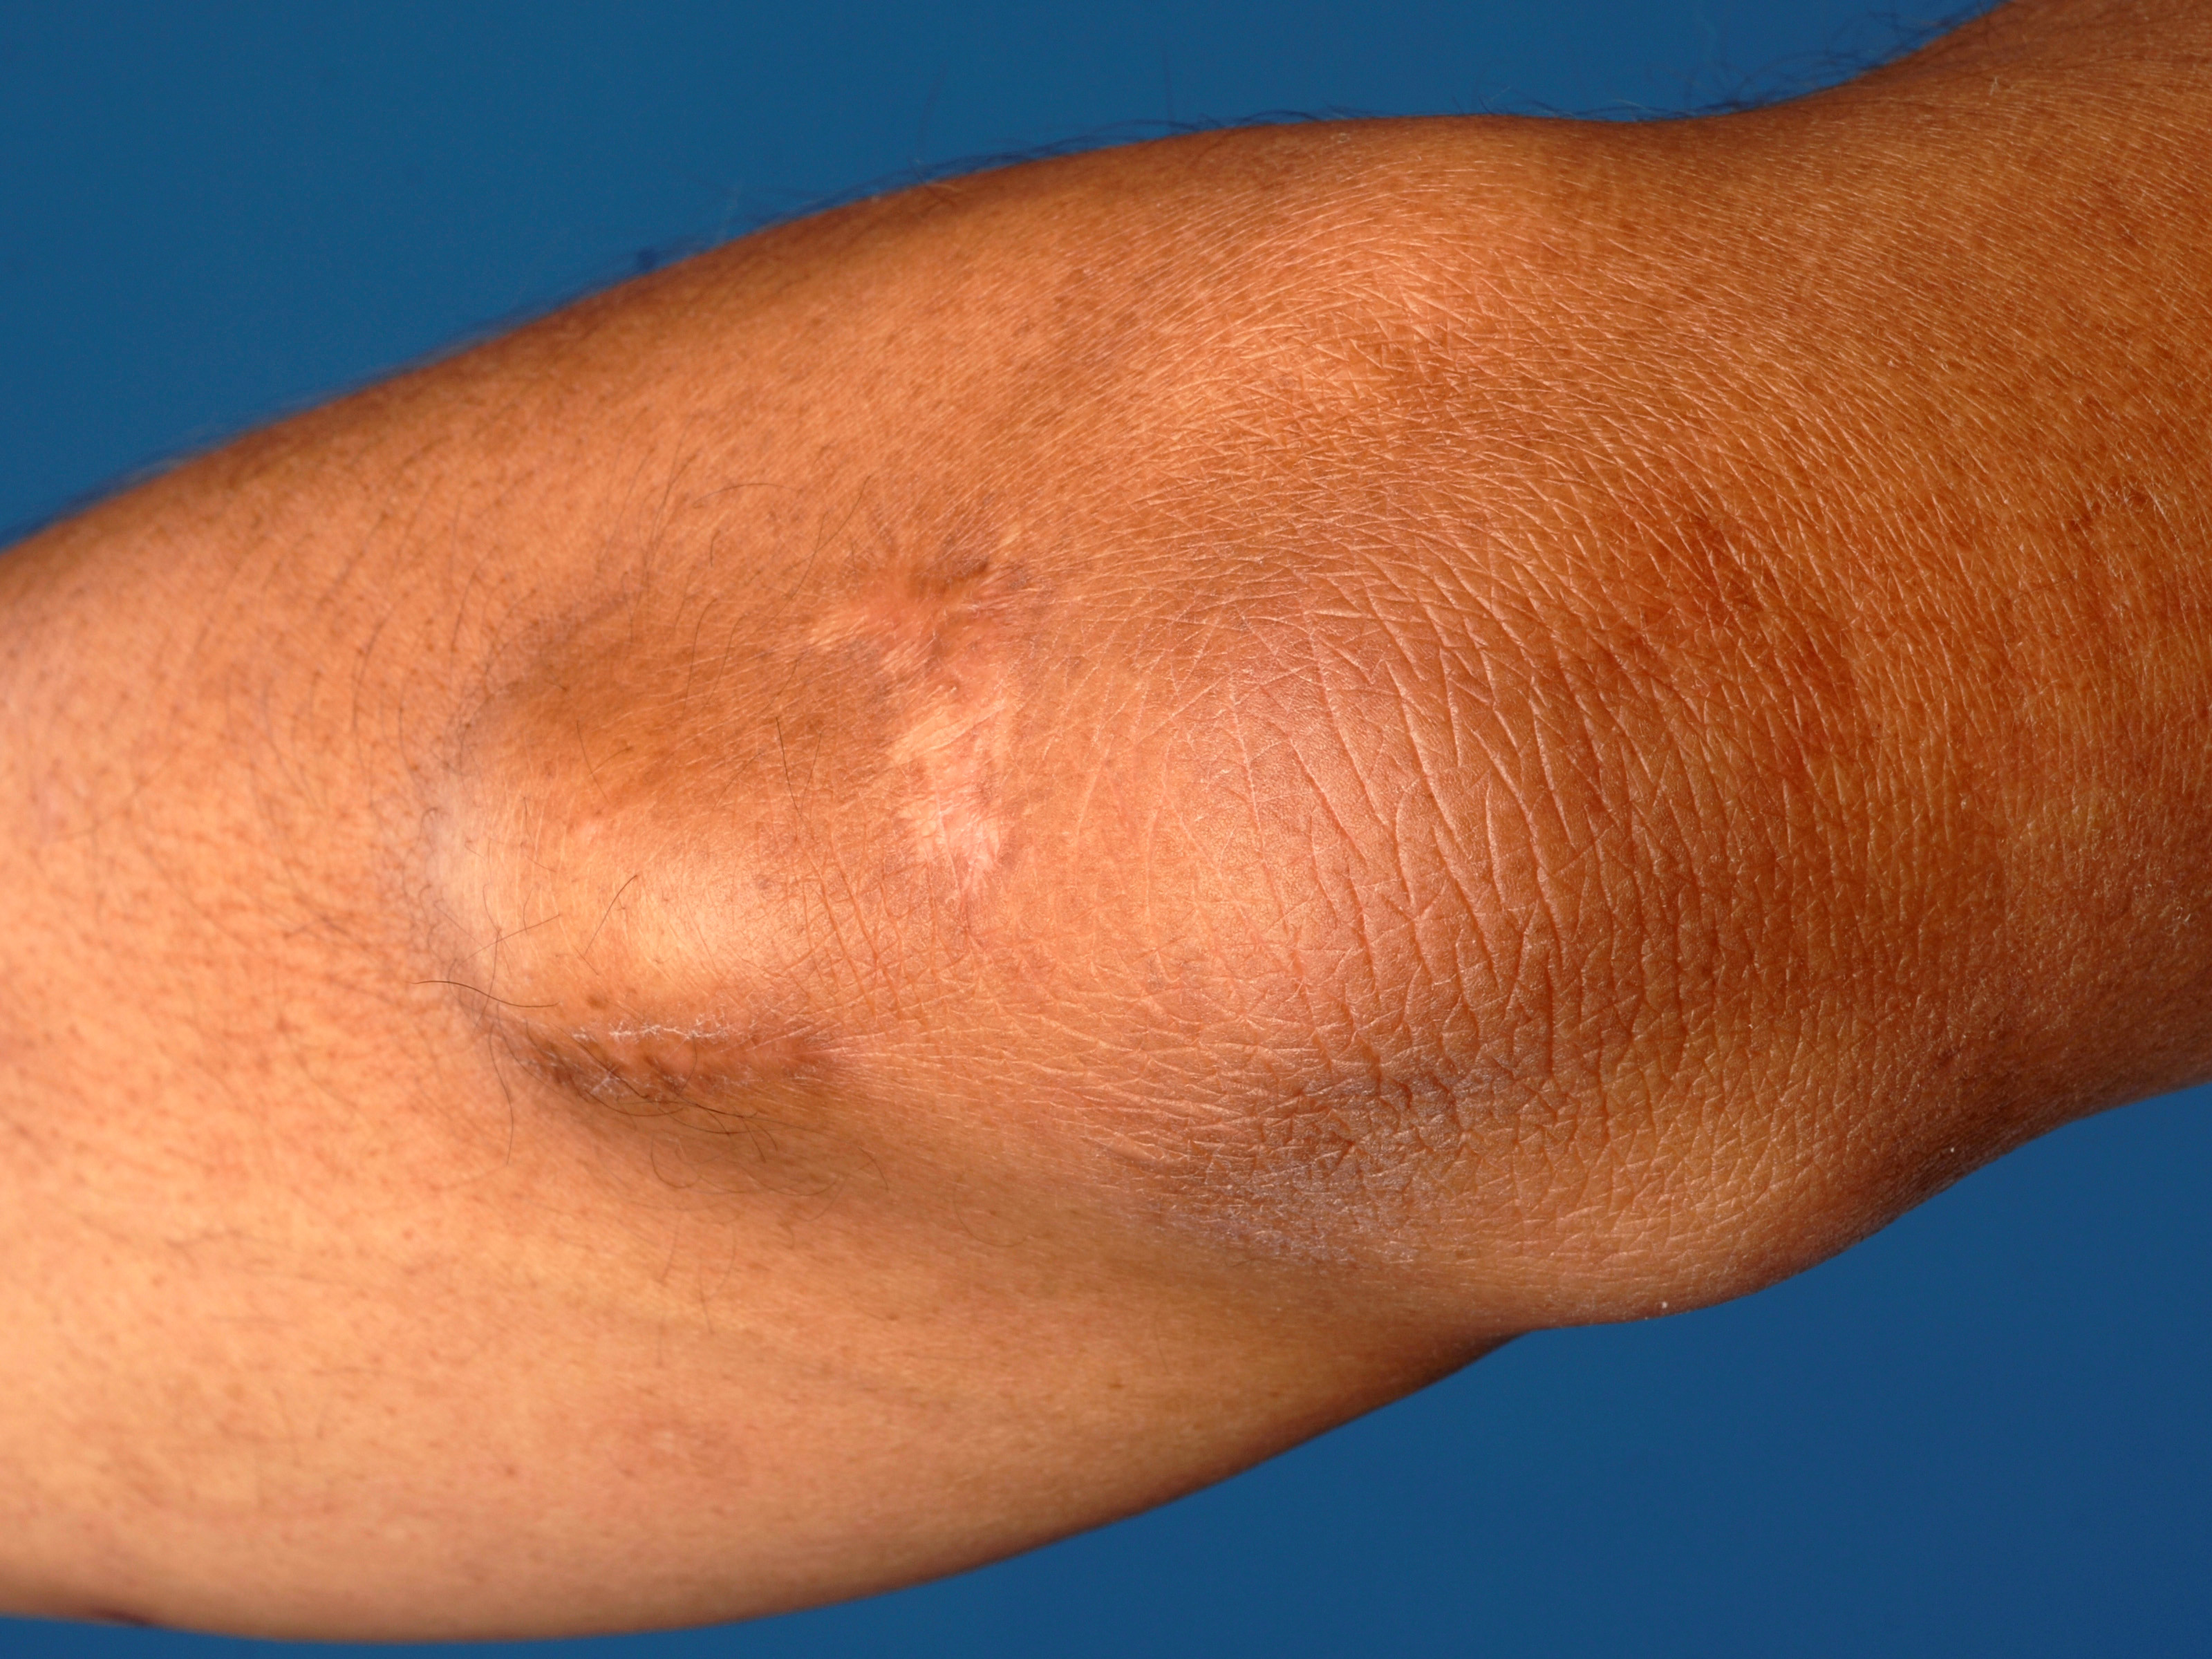

Adipositas dolorosa (synoniemen: M. Dercum, Dercum disease, juxta-articulaire adiposis dolorosa (rond de knieën), lipomatosis dolorosa, adiposalgia, lipalgia) is voor het eerst beschreven in 1892 door Francis Xavier Dercum in Philadelphia. Het is een zeldzaam progressief syndroom gekenmerkt door multipele pijnlijke lipomen, voornamelijk op armen, romp, en peri-articulair in de weke delen. De lipomen zijn pijnlijk bij palpatie (buitenproportioneel in vergelijking met afwijkingen), maar ook spontaan. De lipomen zijn progressief in grootte en aantal, de pijn neemt toe, en is soms niet te onderdrukken met normale analgetica. De pijn kan invaliderend zijn, en is vaak moeizaam behandelbaar. Het betreft meestal post-menopausale vrouwen (man:vrouw 1:30) met obesitas, en wordt geassocieerd met (neurologische) zwakheid, en psychiatrische stoornissen (depressiviteit). Etiologie: onbekend, de pijn wordt mogelijk veroorzaakt door zenuwcompressie van groeiende lipomen. Waarschijnlijk autosomaal dominant overervend, maar meeste gevallen zijn sporadisch/solitair voorkomend. Prognose: chronisch en progressief.

adipositas dolorosa (Dercum disease)

m. Dercum